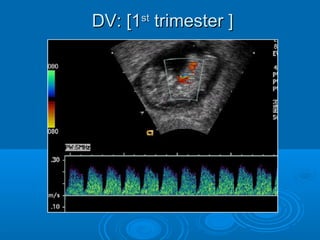

DV: [1st trimester ]

Abnormal blood flow demonstrated as

reversed a wave in the ductus

venosus is seen in 80 % of fetuses

with trisomy 18 and 5 % of euploid

fetuses.

CAUTION:

 DV sampling in 1st trimester is only

indicated if NT is abnormal